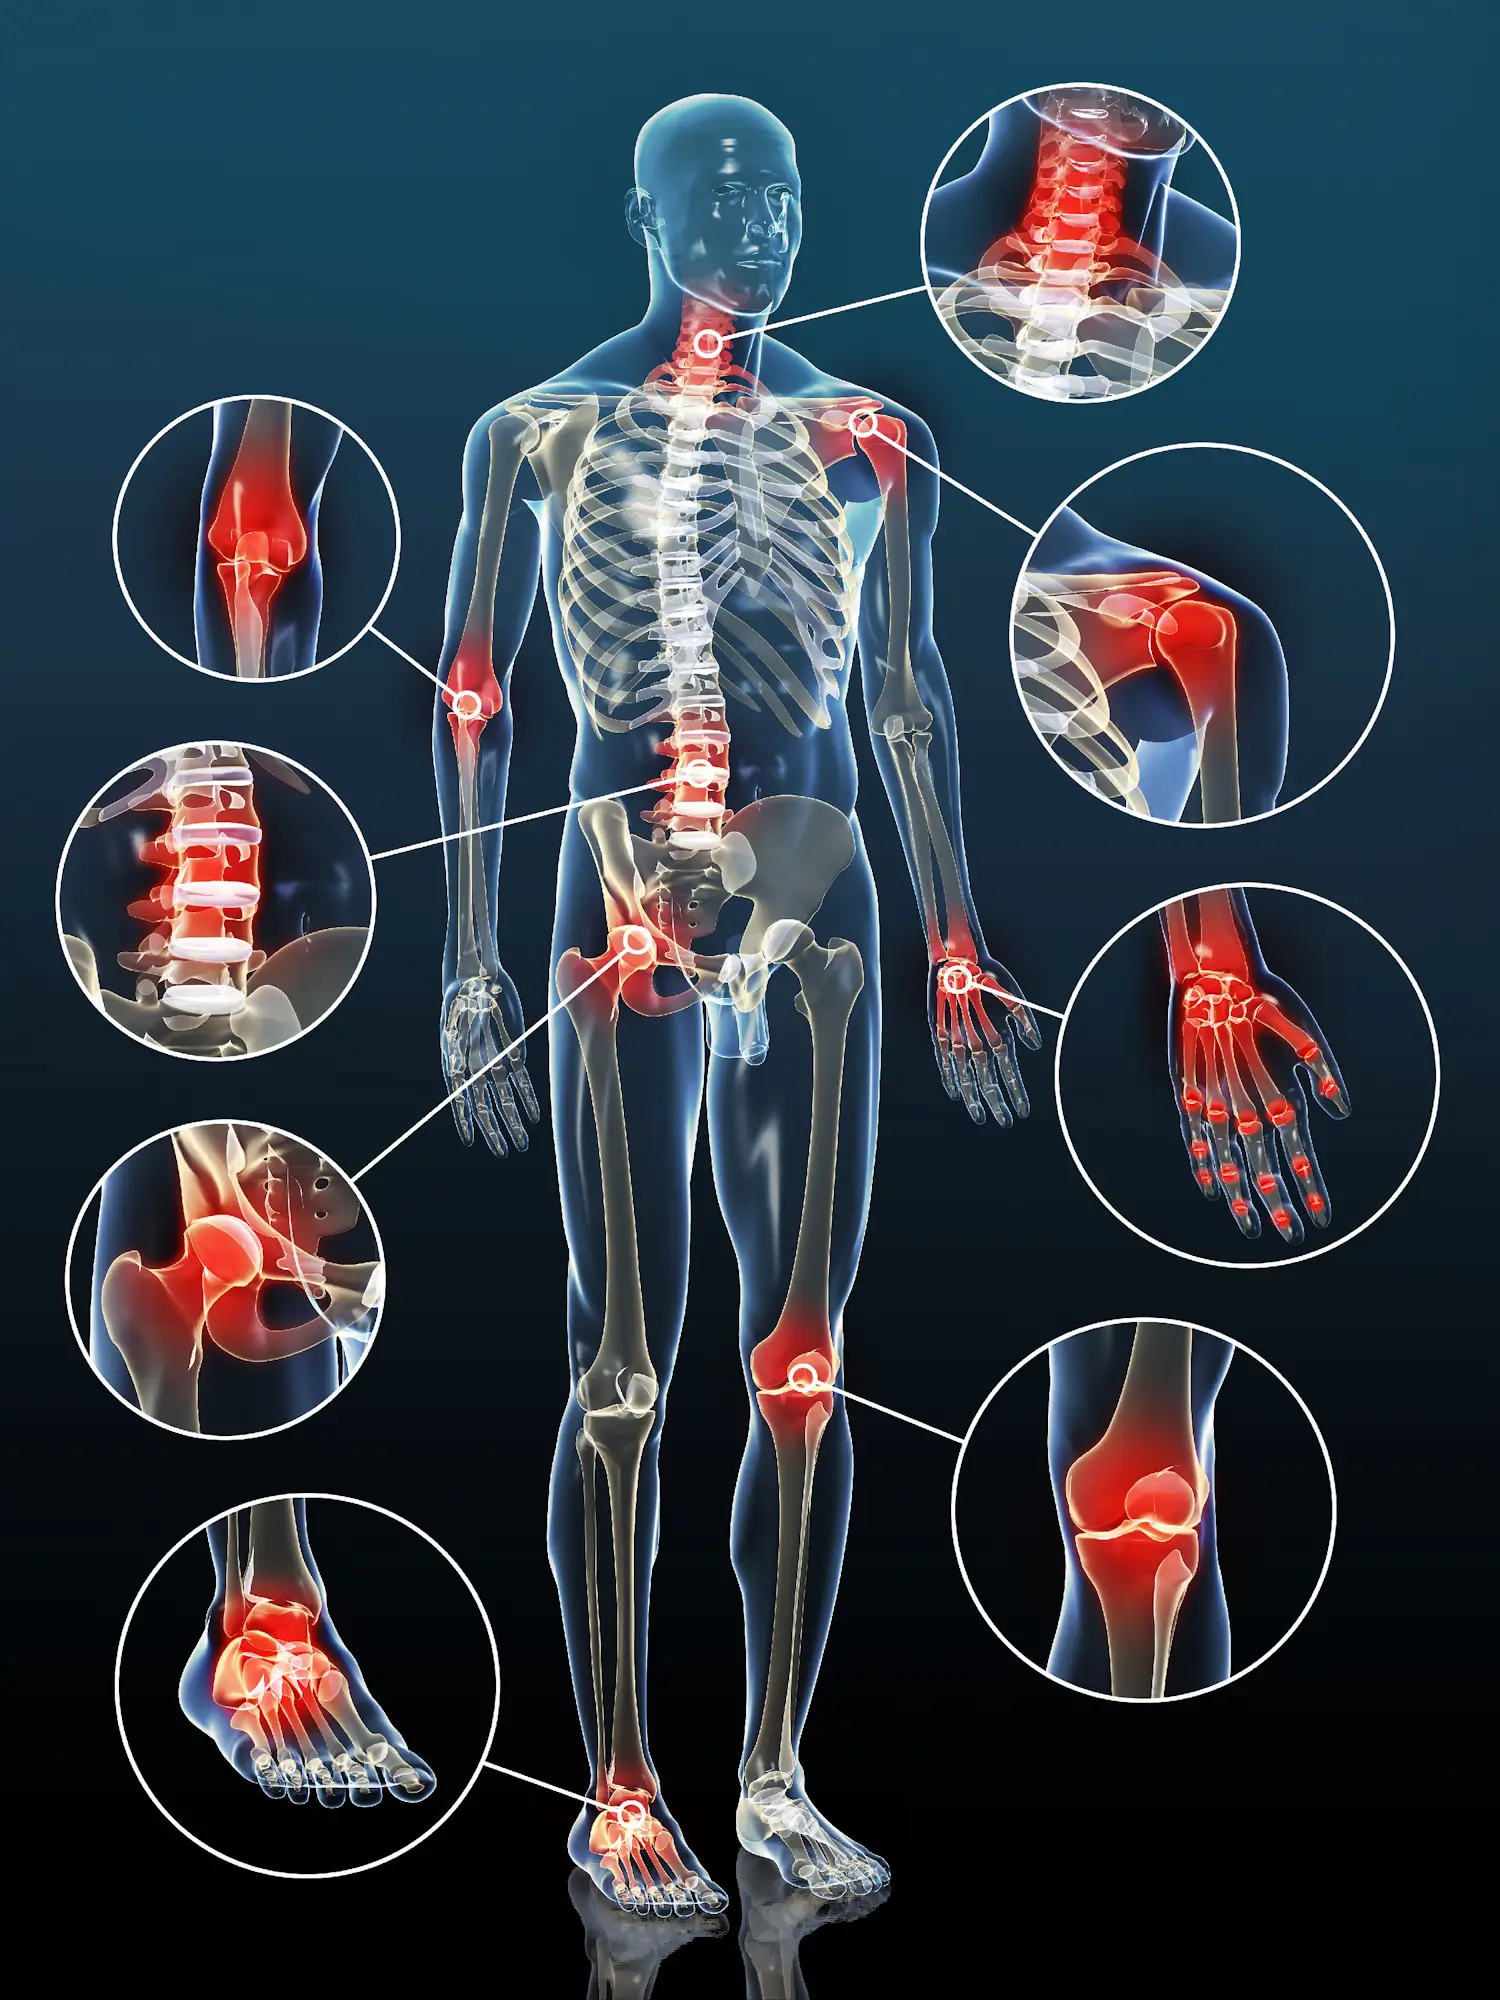

Опорно-двигательного аппарата тред! Аноним 06/11/25 Чтв 16:01:08 1647791 Ответ

image.png 2994Кб, 1500x2000

image.png 14704Кб, 3840x2160

image.png 3967Кб, 1920x1080

Странно что такой важной и сложной теме уделено так мало внимания на этой доске. Помимо того что у любого человека после 30 лет он начинает разваливаться, а у большинства из-за сидячего и неправильного образа жизни есть какие-либо проблемы с ним, найти реально рабочие и честные методы / упражнения / практики почти не представляется возможным, а уж про средних врачей в РФ я вообще молчу. Сам бегал по врачам с болями в тазобедренном суставе и после кучи обследований и направлений туда сюда ничего из этого не выудил и пришлось самому методом проб и ошибок искать решение в интернете. По итогу помог один набор упражнений на мобильность таза и одно упражнение с экспандером. Найти это было нереально сложно и я уж промолчу о том сколько нерабочего говна я перепробовал прежде чем найти что-то что реально бы работало для меня.

В связи с этим предлагаю организовать этот тред обсуждений, где аноны будут либо делиться своими найденными методами решения проблем с ОДА, либо искать эти решения, спрашивая итт советов и проходя путь к здоровому, мобильному и функциональному телу.

Аноним # OP 06/11/25 Чтв 16:02:44 1647792

Тема еще такая сложная от части из-за того как в нашем организме все связано. ОДА буквально система, к которой нельзя подходить не систематически. У меня после фикса тазовых болей внезапно перестало щелкать левое плечо, которое хрустело кучу лет и я думал что это нормально

Аноним 24/12/25 Срд 22:27:42 1653039

Действительно странно, что подобного треда нету на этой доске. Я вот плоскостопием своим хотел бы заняться, думал тут тред какой-нибудь будет чтобы самому инфу не искать. Но видимо придется самому разбираться. Попозже отпишу мб еще